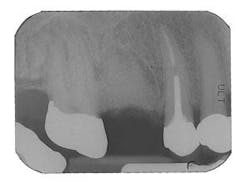

Figure 6 - Same patient with hopeless Tooth No. 3

Figure 7 - Extraction Tooth No. 3 / Perioglas graft